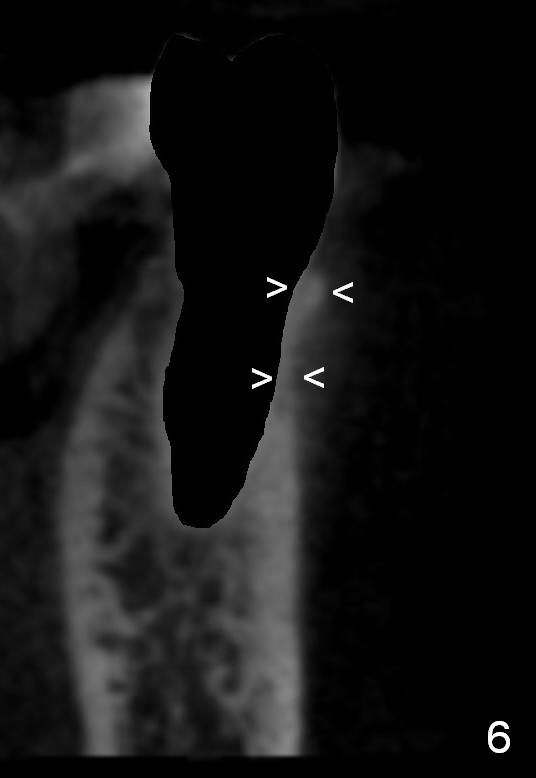

CT sagittal section of a similar case shows that the root is also long, but curved (Fig.4). A 4.5x14 mm implant is slightly longer than the root. The apex of the implant has distance to the underlying nerve (N). The coronal section shows that the implant should be placed lingually (Fig.5 L), since the buccal (B) plate is thin (Fig.6 between arrowheads). The first drill (2 mm) is to be placed lingually (Fig.7 red arrow). When the implant is placed, there should be a buccal gap, to be filled with bone graft (Fig.5 red circles).